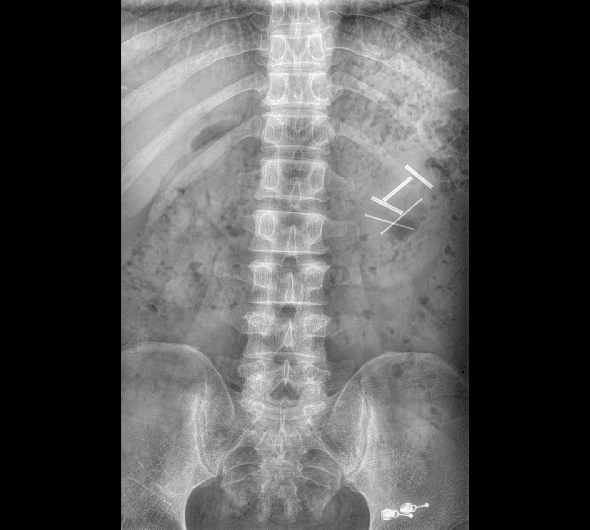

临床图像